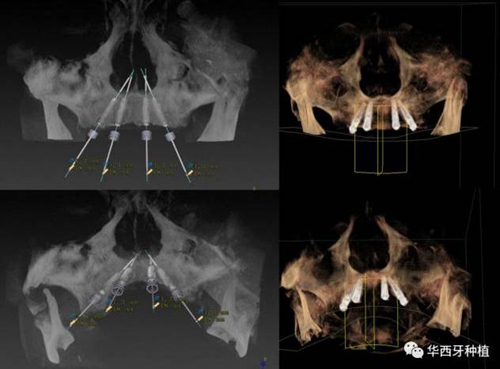

對于傳統(tǒng)的all-on-four術(shù)式,吳教授加入了微創(chuàng)的指導(dǎo)思想,設(shè)計時同樣加入數(shù)字化三維重建與修復(fù)一體化設(shè)計,增加了手術(shù)的可控性,同時極大減輕了患者的創(chuàng)傷程度,縮短了修復(fù)周期。

但是,他同時提到了此種修復(fù)方式操作難度要求很高,僅適合有經(jīng)驗的種植醫(yī)生操作。

演講結(jié)束前,吳教授再次提到了數(shù)字化對口腔全口牙缺失種植修復(fù)一體化的重要性,構(gòu)建一體化的數(shù)字化種植修復(fù)流程,不僅能輔助手術(shù),更是簡化修復(fù)和確保遠期療效的一把利器。